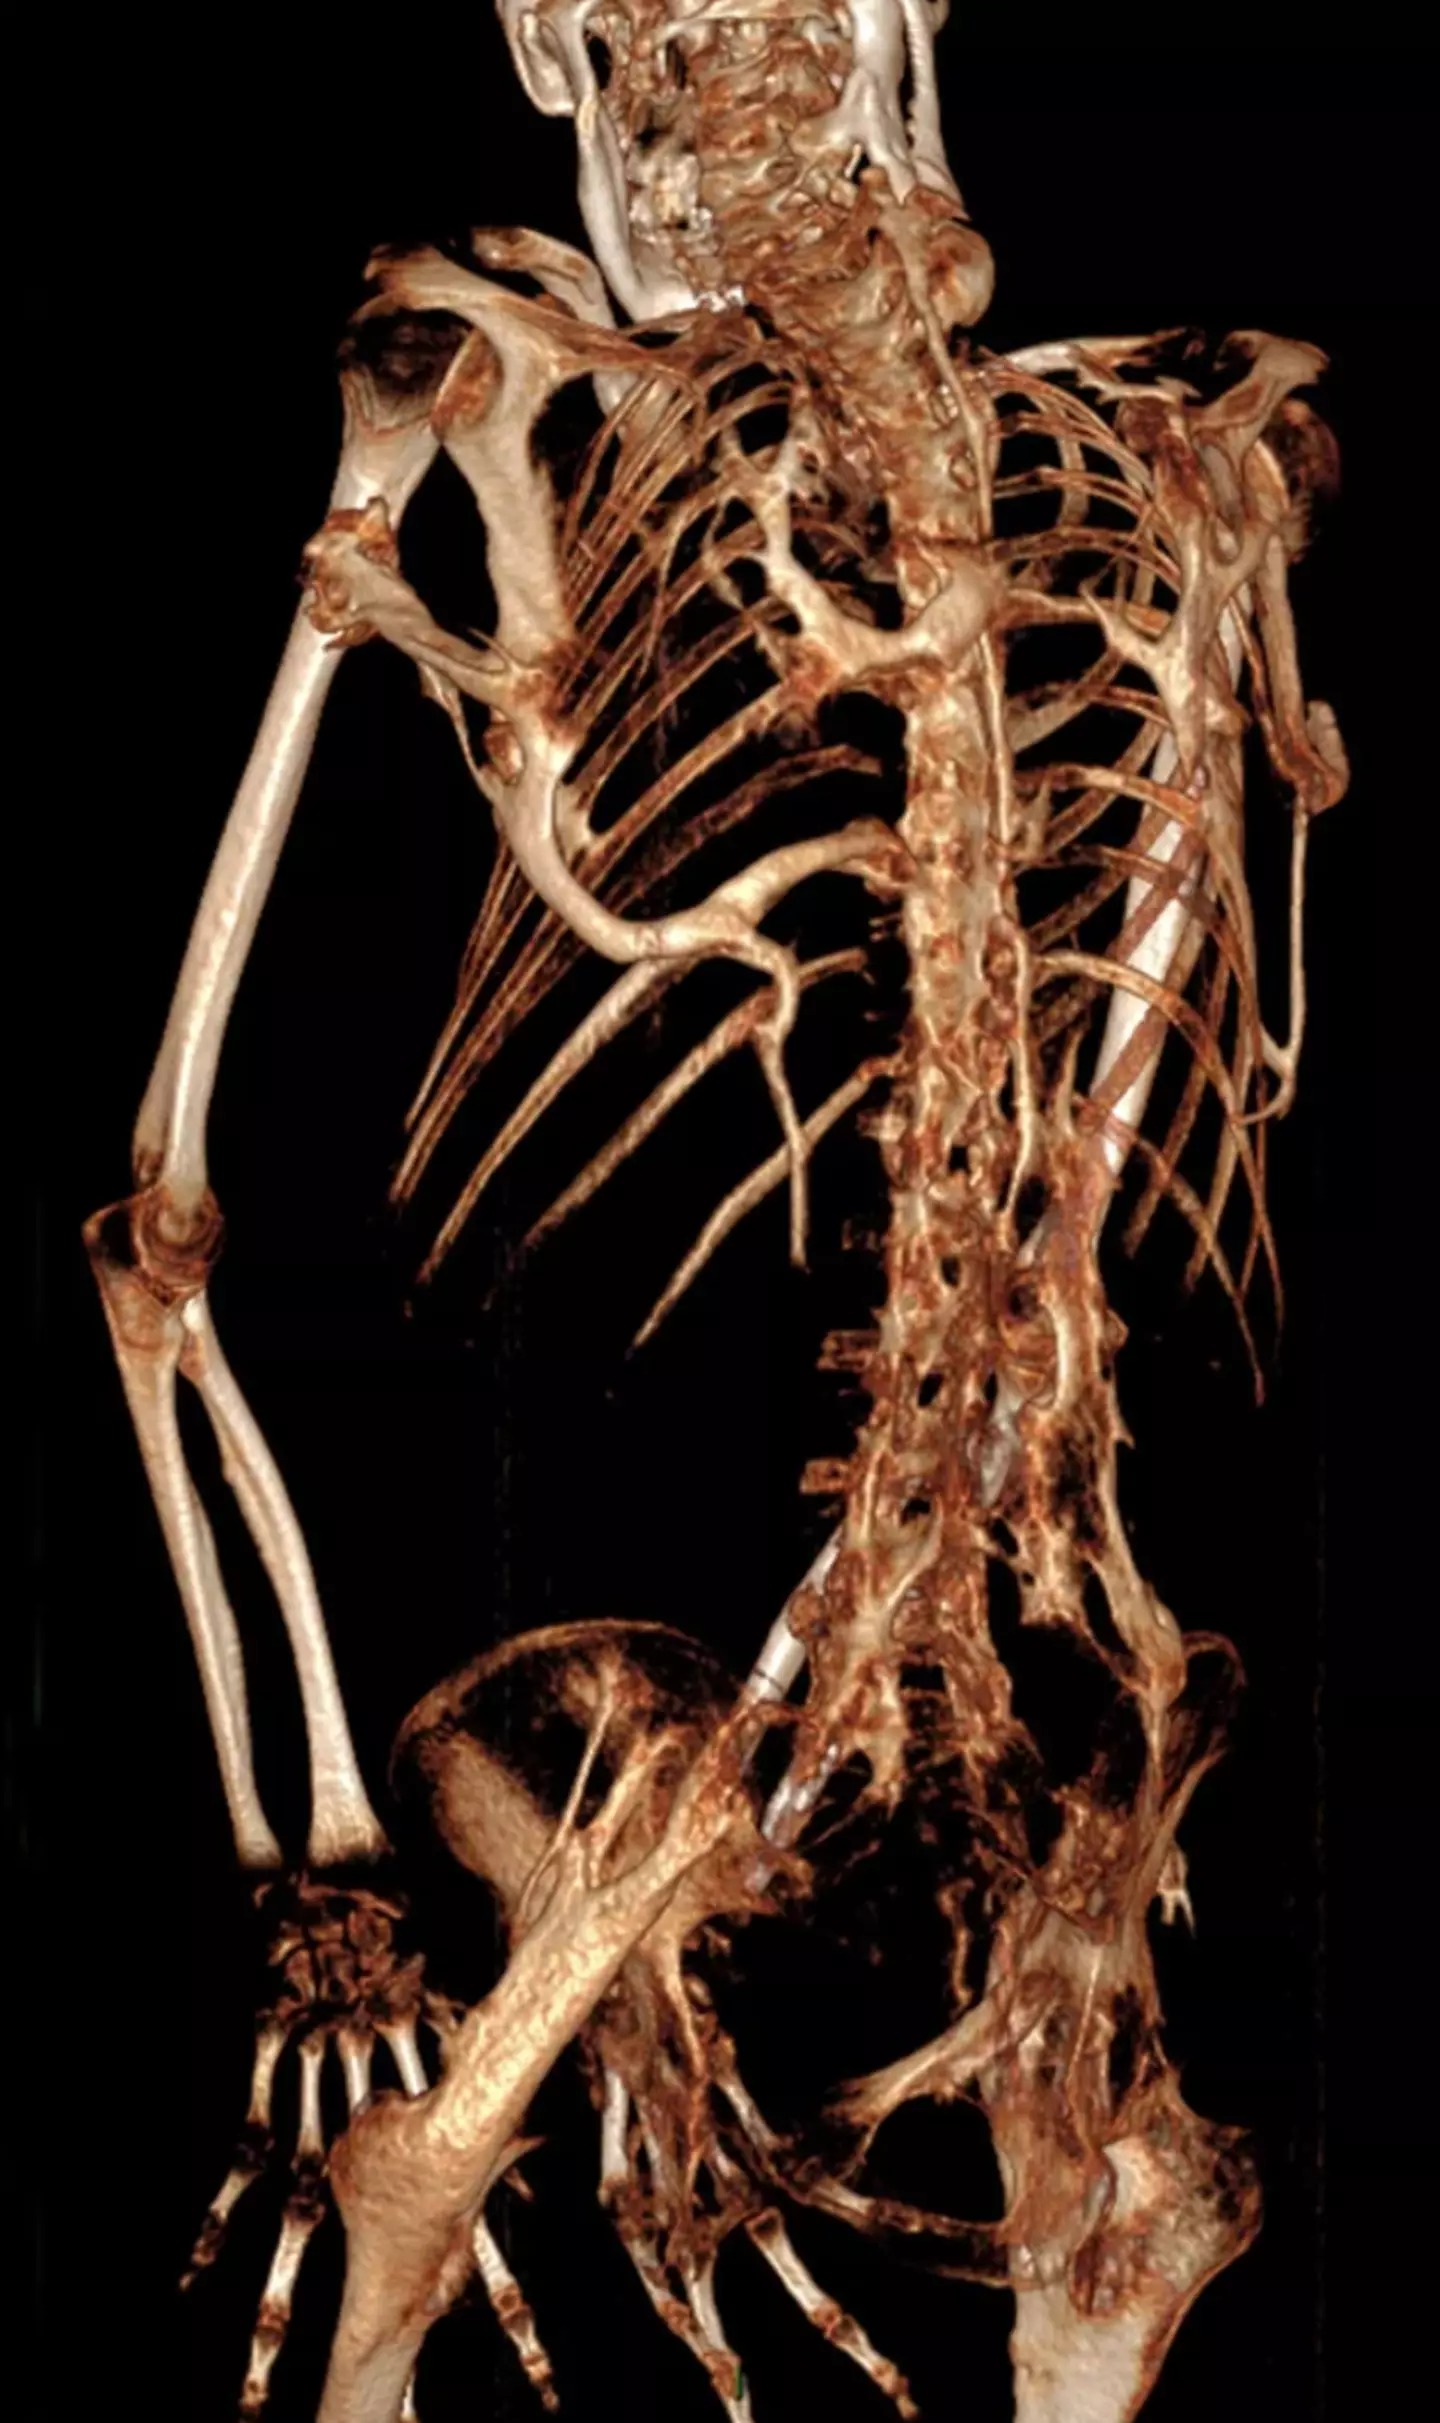

Known by its scientific name Fibrodysplasia ossificans progressiva (FOP), this musculoskeletal condition causes the muscles and tendons to transform into bone through a process known as Ossification. It's said to create a second 'skeleton' of extra bone around the muscles and other organs.

X-ray photos show just how uncomfortable this disease must be as sharp, jagged bones encase the person's entire body, more so in some places than in others.